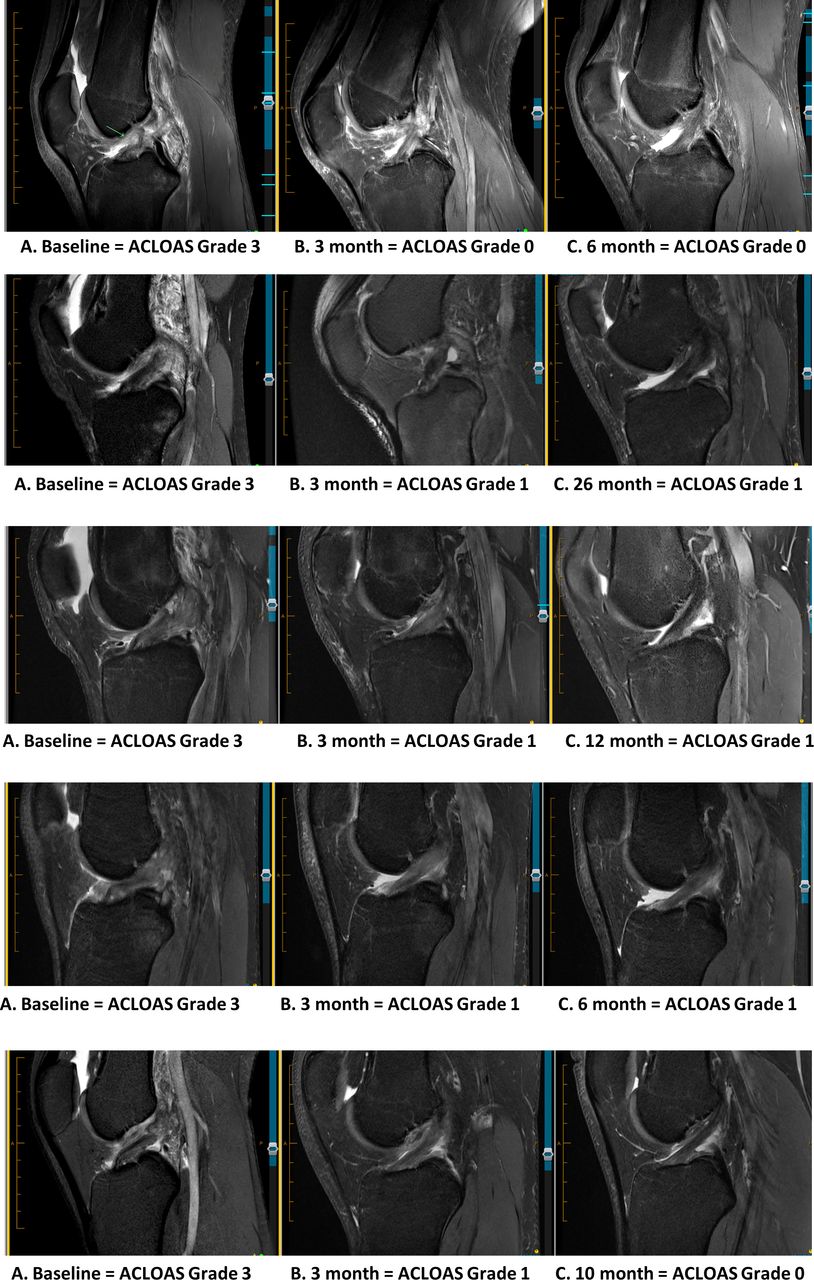

在第 12 周后的随访中,研究人员对患者的膝盖进行了磁共振成像 (MRI)。 他们发现 90% 的患者有 ACL 愈合的迹象。 也就是说,ACL 是连续的或重新连接的。 三个月时的愈合与 12 个月时膝关节功能的改善、生活质量的改善以及重返运动的比率较高相关。